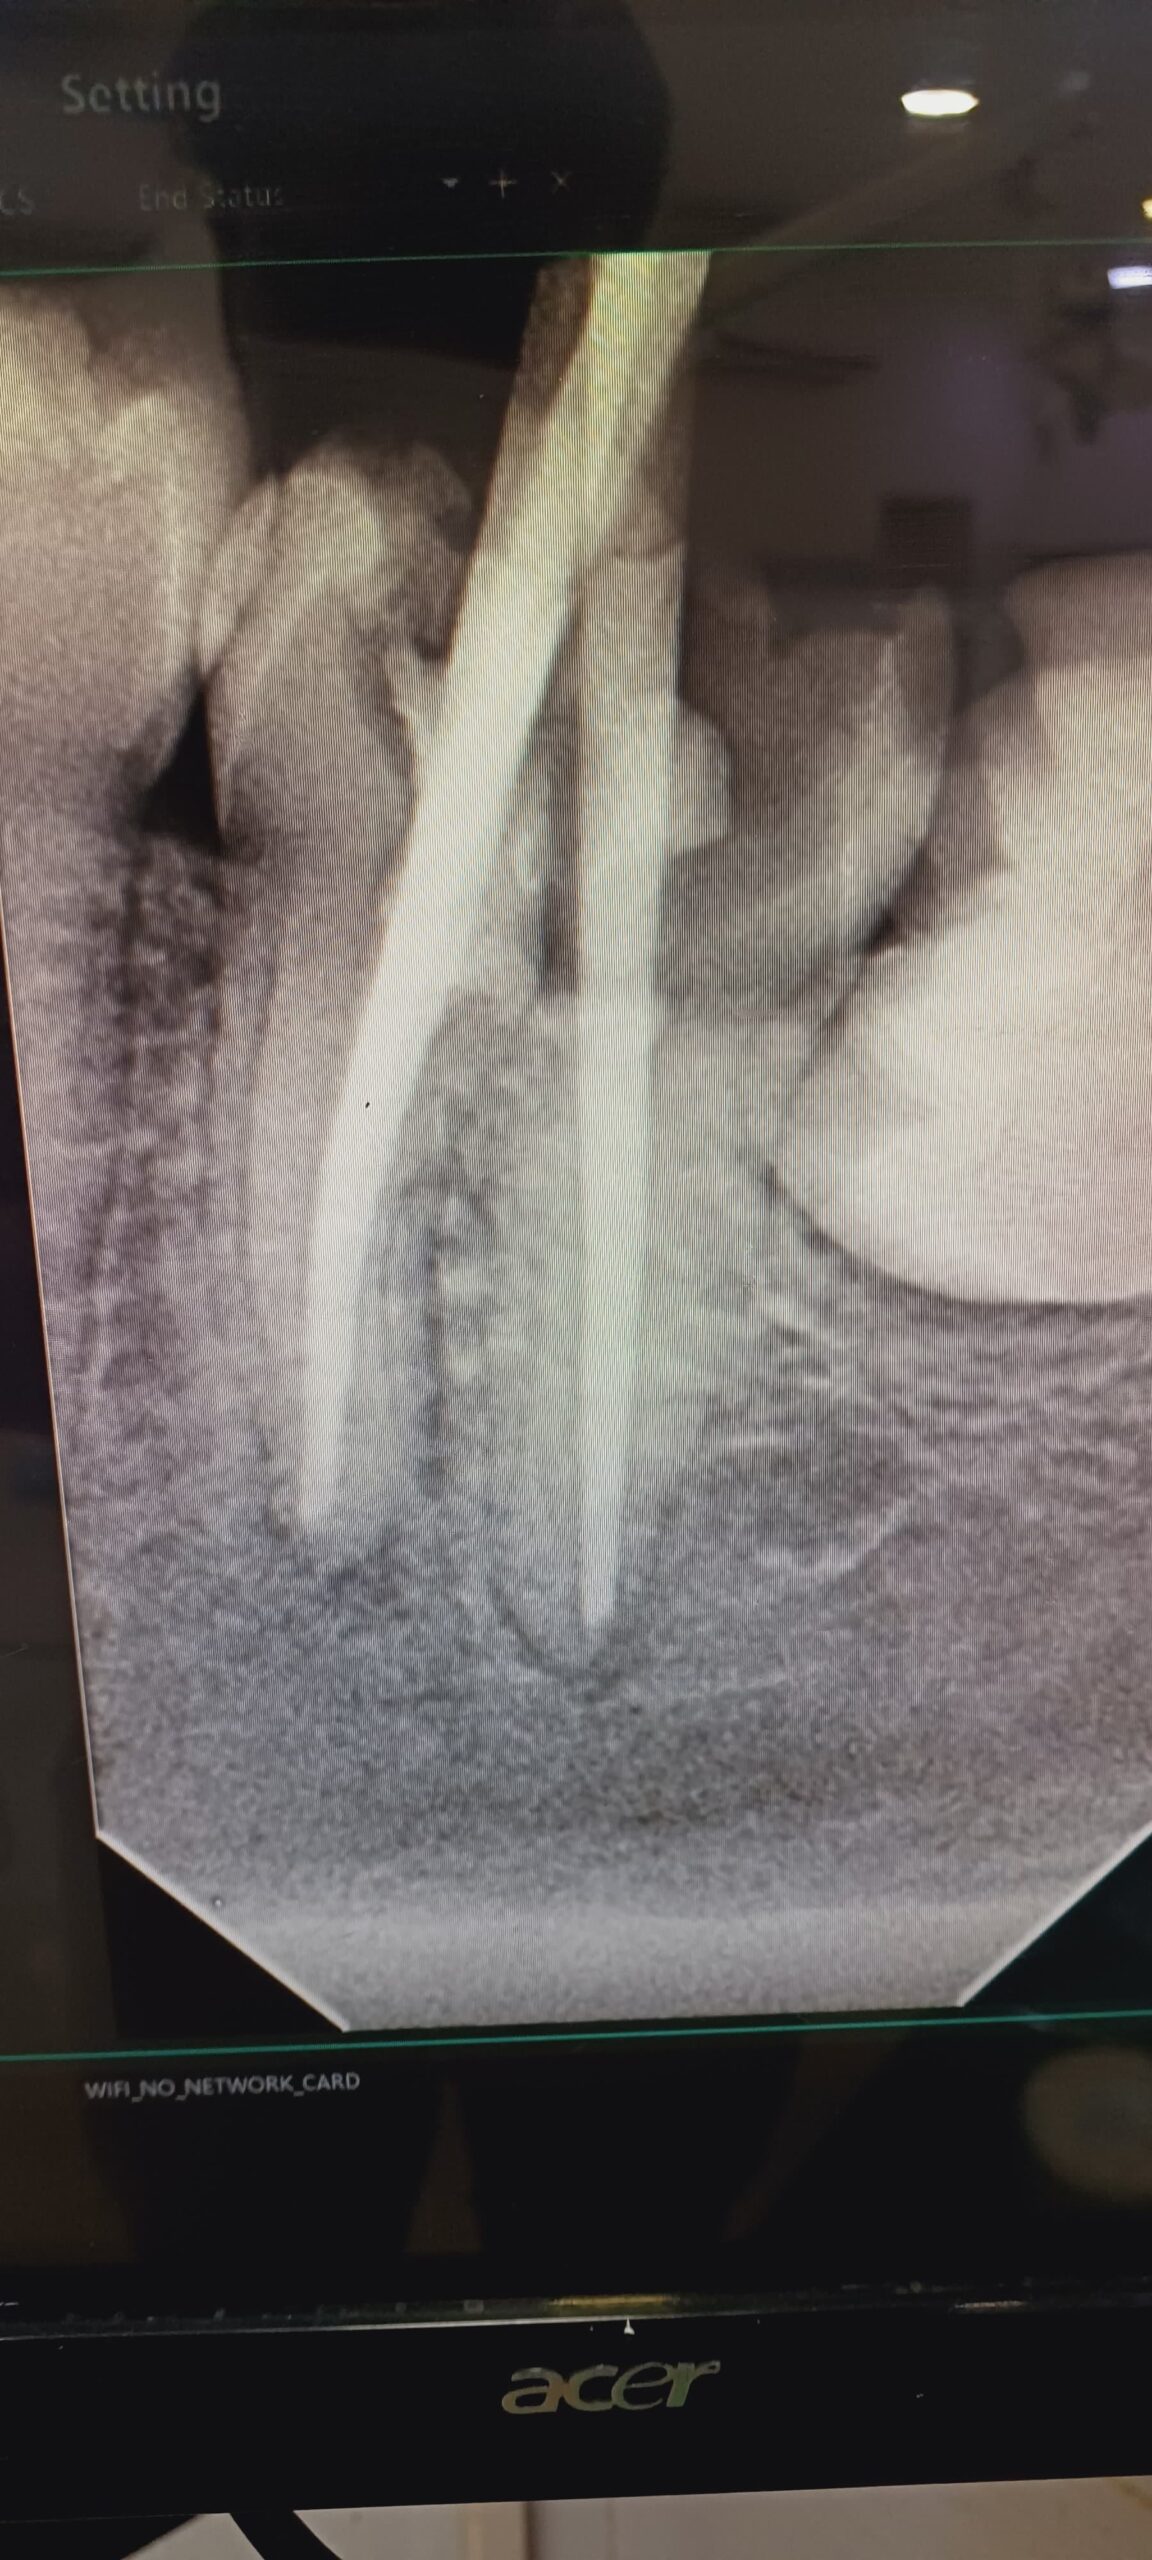

Gallery Home Gallery Pulpectomy Broken File Retrieval Root Canal Treatments Orthodontic Treatments Wisdom Teeeth Removal